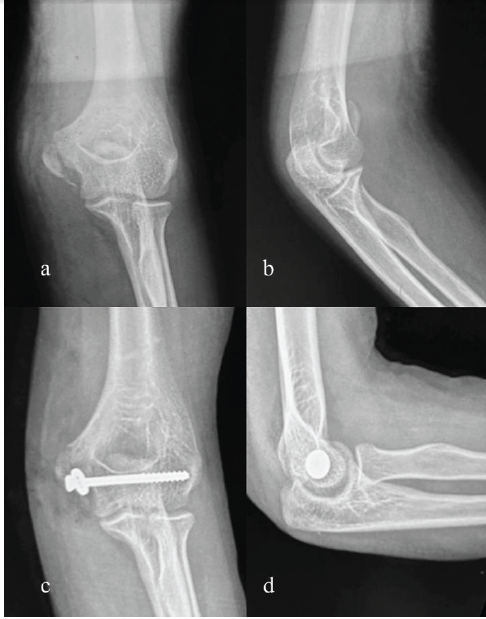

(CC screw) A 70-year-old female sustained fall onto her left elbow. The patient was previously operated with radial head replacement. Examination revealed swelling, pain, and limited flexion. Radiographs demonstrated a large medial epicondyle fragment and a radial head implant. The fracture was fixed with a single 4.5 mm CC screw after anatomical reduction. Union was evident at 14 weeks; she regained a 0–110° arc of motion, with mild persistent stiffness but independence in daily activities (Fig. 5).

Figure 5: Pre-operative and post-operative X-rays right elbow (a) pre-operative X-ray right elbow anterior-posterior (AP) view, (b) pre-operative X-ray right elbow lateral view, (c) post-operative X-ray right elbow AP view, (d) post-operative X-ray right elbow lateral view.